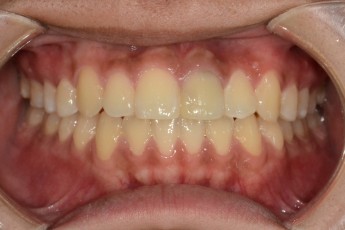

BEFORE & AFTER

- 과개교합교정